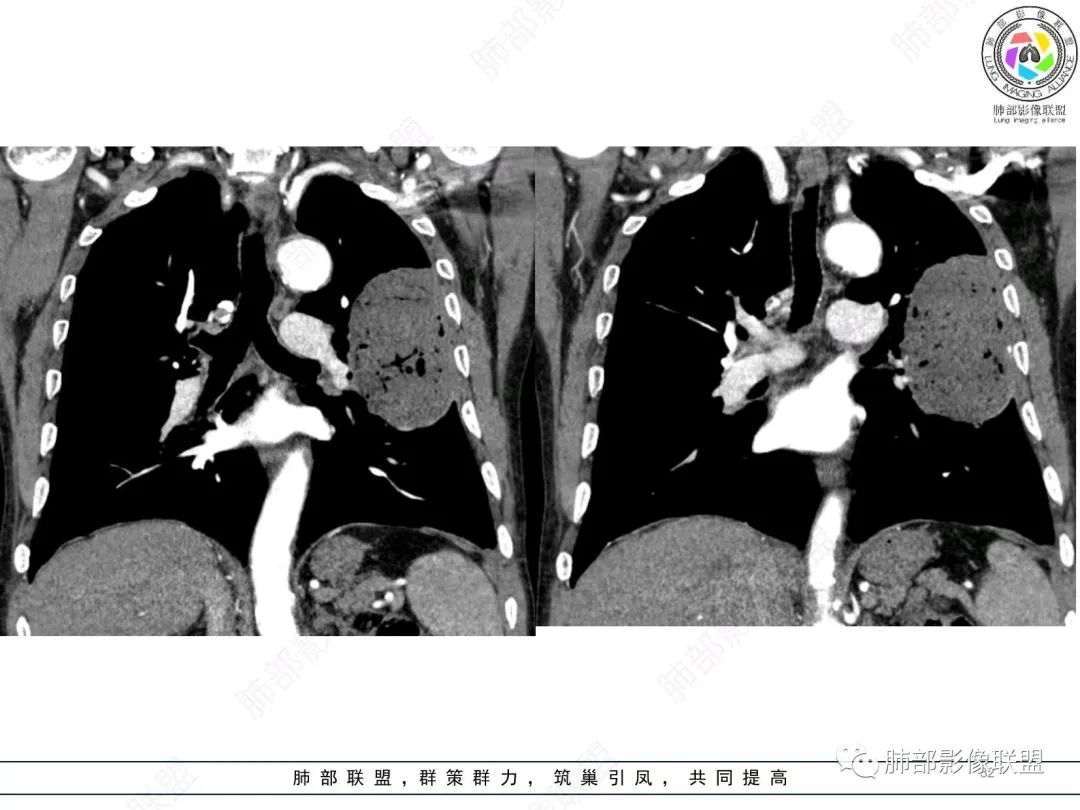

老年男性,糖尿病病史,消瘦、乏力三个月,影像表现左肺上叶胸膜下团块,有一定张力,内部疏松,可见支气管影及坏死区,增强病灶边缘环形强化,内部未见强化,考虑炎性肉芽肿病变,隐球?奴卡?放线菌?鉴别淋巴瘤。

糖尿病史,慢性病程,左肺巨大肿块,跨叶生长,肿块近端可见充气支气管征及悬浮气泡,轻度圴匀强化,病变长轴与胸膜平行,炎性标志物正常,考虑放线菌,其次淋巴瘤

老年男性,糖尿病病史,消瘦、乏力三个月,肿瘤标志物高。左肺上叶胸膜下肿块,边界清晰,可见支气管影及坏死区,增强病灶边缘强化,内部未见明显强化,邻近胸膜有累及,考虑恶性,建议穿刺活检。

我再建一下血管。支气管进入,但是近端推移,堵塞

近端支气管堵塞、推移为主

肺动脉推移为主,边缘部分进入